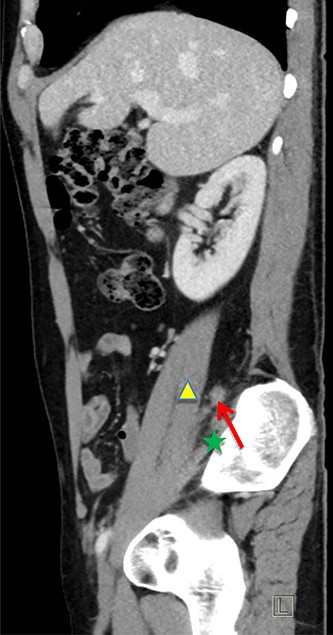

The patient was re-admitted and examination revealed a soft abdomen with localized rebound tenderness in the right iliac fossa. A computed tomography (CT) abdomen was requested and a referral made to the surgical team. The CT scan illustrated AA with the appendix located posterior to the ileo-psoas muscle (Figs 1–3). A diagnostic laparoscopy was performed, which revealed the head of the inflamed appendix herniated posterior to the psoas muscle in a cavity, (~25 mm deep and 10 mm in diameter) that could not be dissected laparoscopically (Fig. 2). Therefore, an uncomplicated open appendectomy was performed and the patient was admitted for post-operative observation. Recovery was uneventful and the patient was discharged without follow-up.

Sagittal CT image. Inflamed appendix (red arrow) positioned between psoas (yellow triangle) and iliacus muscles (green star).